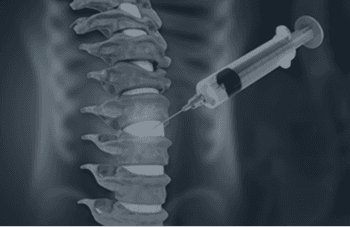

At New York Elite Orthopaedics, our board-certified specialists provide advanced diagnostic, surgical, and non-surgical care for a full range of musculoskeletal conditions. Whether you're recovering from a sports injury, managing joint pain, or preparing for a life-changing procedure, our fellowship-trained experts deliver the focused, individualized care you deserve — using the latest techniques and technologies to help you move with confidence again.